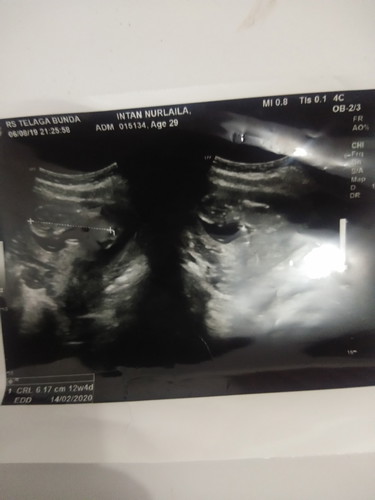

bunda2 mau nnyak itu kok bby nya wjahnya ke bawah ya. mohon jwban nya ya bunda, smlm lupa nnyak dokter smpai rmh jd pnsaran sy kok bs bby nya kebalik gt bnda

Ga kenapa-napa itu bun.. Kalo masih kecil memang masih sering muter-muter. Terus sudut pengambilan posisi saat USG juga ngaruh. Foto USG kan biasanya bayinya horizontal gitu kan ya bun.. Padahal sebenernya di dalam rahim, dia vertikal. Kepalanya ada di bawah. Jadi posisi foto gaperlu dikhawatirkan

Bayi mah muter2 di dalam rahim bun.. berenang2 urusan posisi mah suka2 dia apalagi kalo masih di bawah 32w nah kalo udh diatas 32 w baiknya posisi kepala udh dibawah

Iy dia lg hadep bawah kali bun.. Masi kecil bgt itu si dedenya๐